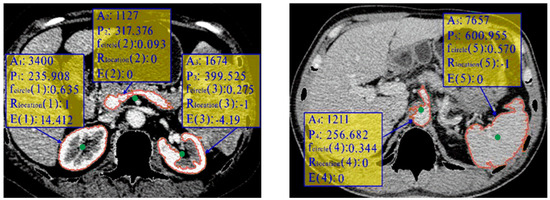

Figure 6 shows five contours with red color in two images from two different sequences. The green points are their centroids. By examining the features listed in the yellow rectangle, we can observe that the location restriction and circularity feature help filter out non-kidney regions (regions 2, 4, 5) and a segmentation error in region 3. The final selection of the most reliable contour is based on the highest E value, which corresponds to region 1. This approach ensures accurate and reliable selection of the left and right kidneys, even when they are not on the same slice.

Figure 6. Examples of five contours from two images.